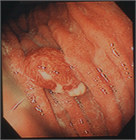

1. ラズベリー様腺窩上皮型胃腺腫は、その名称の通り鮮紅色の表面顆粒状の形態を呈する。参考として内視鏡画像も追加した。

1. 胃過形成性ポリープは発赤調のポリープとして類似のラズベリー様胃腺腫と鑑別を要する。